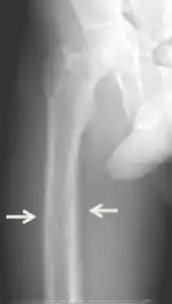

Diagnosis includes both clinical and laboratory investigations. Radiological investigations include looking for signs of bone loss in both the hands and pelvis which is characteristic of tertiary hyperparathyroidism.[8] Other clinical examination can include grading of muscle weakness, which is done by asking the patient to stand from a seated position with their hands folded across their chest.[4][8] Laboratory investigations include evaluating blood calcium and alkaline phosphatase, which are always increased in tertiary hyperparathyroidism. Other common results from laboratory investigations would include decreased vitamin D levels, elevated blood parathyroid hormone and hyperphosphatemia.[9][8][1][4]

Primary hyperplasia of the parathyroid gland, results from both hypocalcaemia and increased phosphate levels by decreasing expression of calcium sensing receptors and vitamin D receptors at the parathyroid gland.[8][4] These decreases in receptor expression lead to hyperfunctioning of the parathyroid. Hyperfunction of the parathyroid gland is thought to exacerbate primary hyperplasia which evolves further to a secondary more aggressive hyperplasia. Histologically, these hyperplasic glands can be either diffuse or nodular.[24] Primary hyperplasia, usually resulting in diffuse polyclonal growth is manly related to reversible secondary hyperparathyroidism. Secondary hyperplasia of the parathyroid gland is more often a nodular, monoclonal growth that sustains secondary hyperparathyroidism and is the catalyst in the progression to tertiary hyperparathyroidism. Nodular hyperplastic glands in tertiary hyperparathyroidism are distinctly larger in both absolute size and weight up to 20-40-fold increases have been reported.[25][26][24]

Parathyroid glands are normally composed of chief cells, adipocytes and scattered oxyphil cells.[27][14] Chief cells are thought to be responsible for the production, storage and secretion of parathyroid hormone. These cells appear light and dark with a prominent Golgi body and endoplasmic reticulum. In electron micrographs, secretory vesicles can be seen in and around the Golgi and at the cell membrane. These cells also contain prominent cytoplasmic adipose.[27][14] Upon onset of hyperplasia these cells are described as having a nodular pattern with enlargement of protein synthesis machinery such as the endoplasmic reticulum and Golgi. Increased secretory vesicles are seen and decreased intercellular fat is characteristic.[27][24] Oxyphil cells also appear hyperplasic however, these cells are much less prominent.